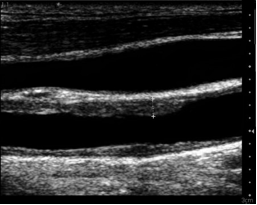

USG é utilizado para avaliar o quê?

Circulação e morte encefálica.

Quais os achados do doppler de carótida normal?

fluxo laminar com maior velocidade no centro (maior atrito na periferia) sem pontos de picos de velocidade.

Como diferenciar a carótida do vaso adjacente no USG? Que vaso é esse?

A jugular interna colaba quando se aplica pressão com o transdutor. A carótida não colaba.

O que fica branco, preto e cinza no USG de carótida?

branco = paredes dos vasos

preto = sangue

cinza = placa aterosclerótica